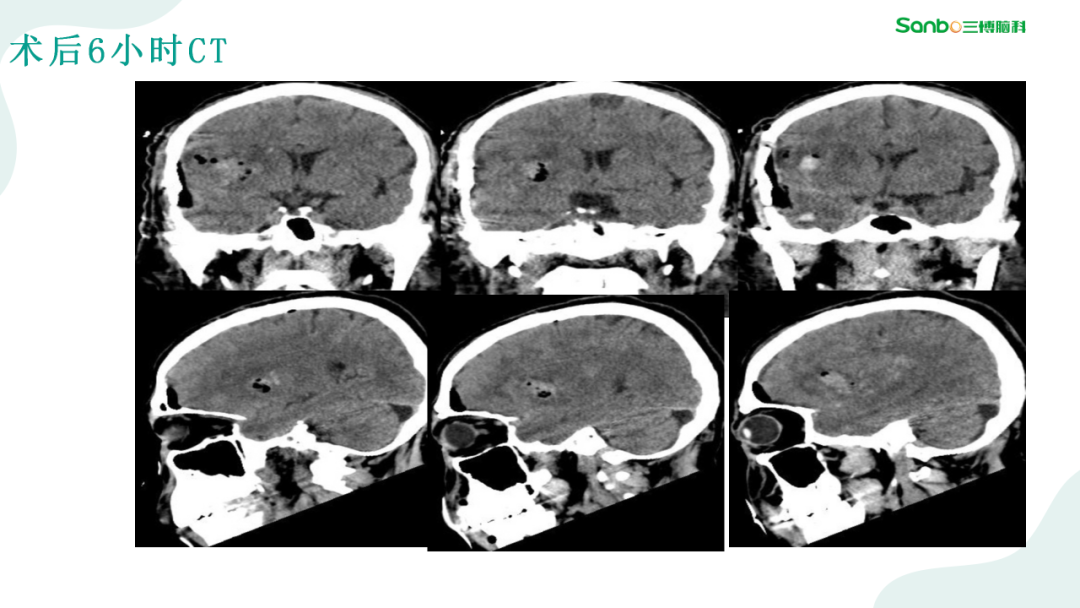

2月28日下午3:00,第二期“健康小课堂”科普活动由神外二科副主任杨海洋围绕《脑血管病的那些事》,给大家耐心讲解了有关脑血管的相关知识,生动的讲课引发在场的热烈讨论,大家纷纷表示受益匪浅。